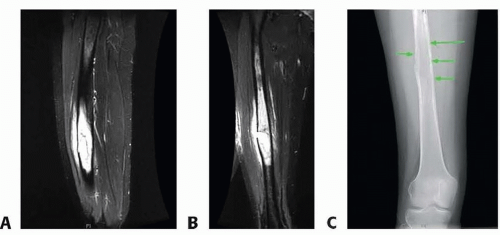

Preoperative imaging of both the recipient and donor sites should include an evaluation of:

Recipient site:

The extent of bone resection, length and diameter of the intercalary defect, and potential soft tissue defect (FIG 2). This allows the surgeon to determine the extent of the tumor burden, traumatic bone loss, or chronic osteomyelitis and plan for reconstructive options.